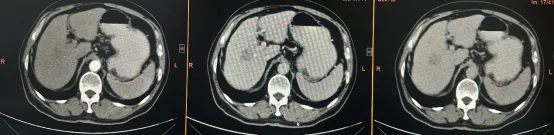

李大爷的肿瘤正好位于肝脏的Ⅴ、Ⅷ段交界处,紧邻门静脉的右前支与右后支分叉部,属于典型的、手术风险极高的中央型肝癌。

面对挑战,陈艳军主任医师团队进行了充分的术前规划和集体会诊,决定迎难而上,实施根治性切除手术。

手术过程平稳顺利,全程仅用时4小时,出血量仅约200ml。术后病理结果确诊为肝细胞癌,切缘阴性,实现了根治性切除。